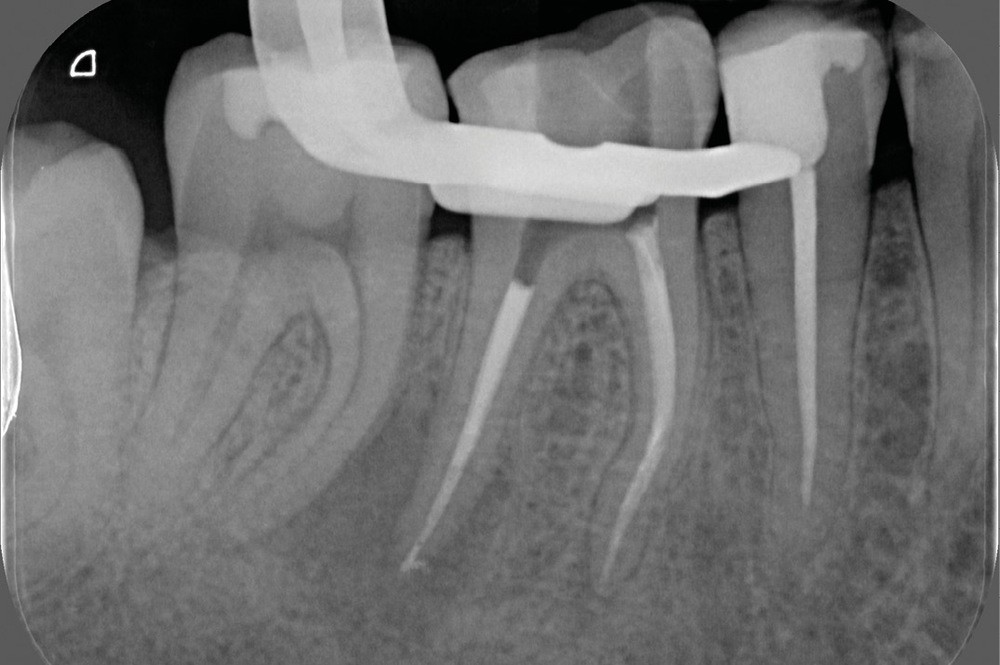

La préparation mécanique est principalement réalisée à l’aide d’instruments NiTi utilisés en rotation continue ou en réciprocité selon une approche corono-apicale. La mise en forme est ainsi plus rapide et respecte mieux le trajet canalaire initial qu’avec une instrumentation manuelle. Le diamètre apical et la conicité de la préparation canalaire font toujours débat. Ils dépendent de l’anatomie initiale et doivent permettre une irrigation efficace sans fragiliser la dent. Ainsi, un diamètre apical de 30 et une conicité de 6 % sont souvent proposés comme objectif minimal à atteindre [3] (fig. 1).